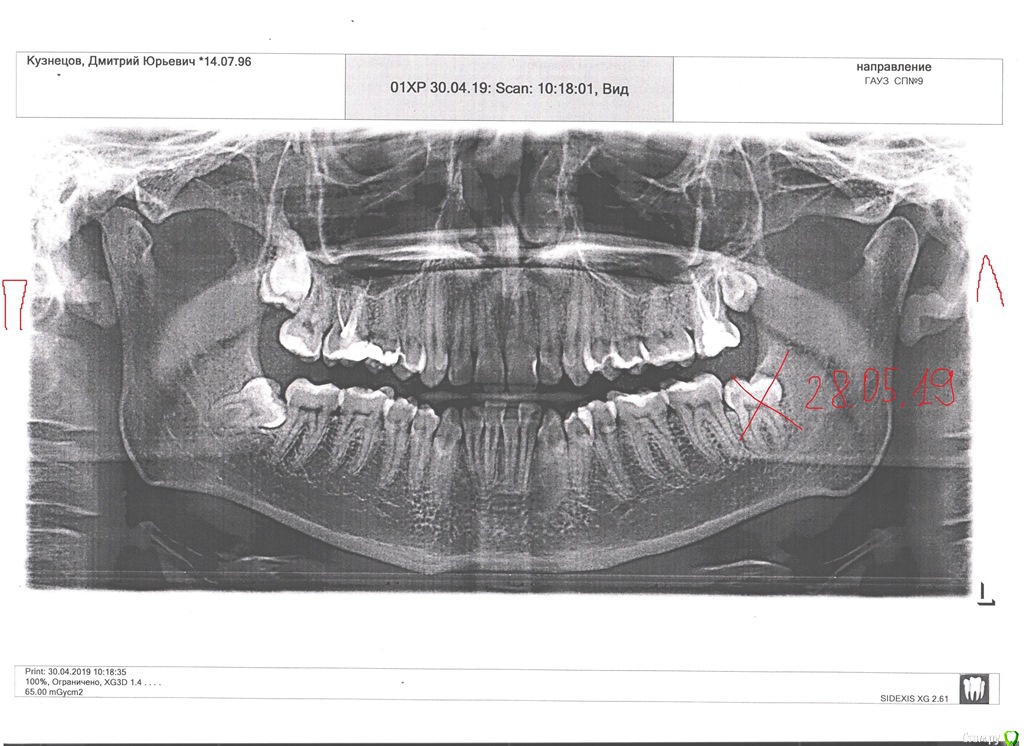

Стоматолог, лечивший шейки, порекомендовала сделать ортопантомограмму. ОПГ посмотрела ортодонт и сказала, что нужно удалить зубы мудрости на нижней челюсти и вновь ставить брекеты.

P.S. В ближайшие дни записан на удаление 8-ки справа внизу, однако зубной ряд справа не искривлён, поэтому я немного сомневаюсь в необходимости удаления. На ОПГ видно, что этот зуб лежит почти горизонтально. Не знаю как это трактовать, как низкую вероятность его роста или высокую вероятность смещения предшествующих ему зубов в будущем...